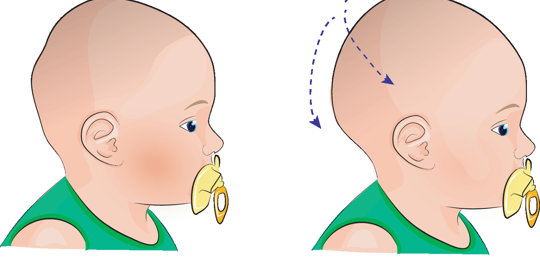

嬰兒枕禿:使用時間與高度標準